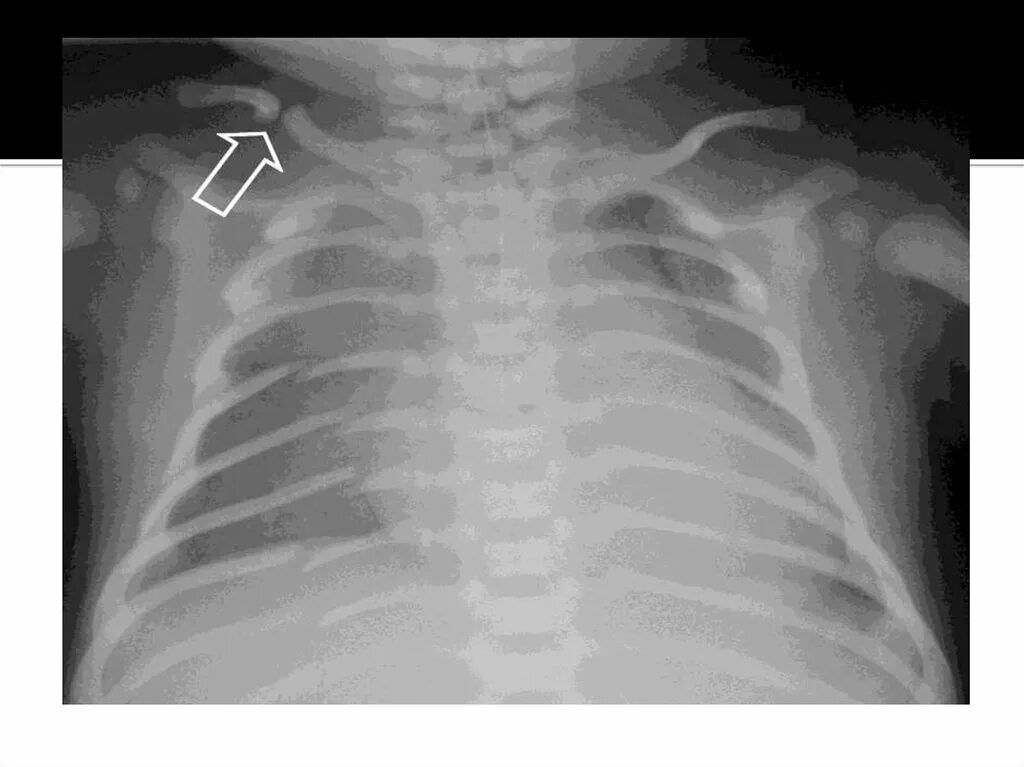

Как лечить сломанное ребро